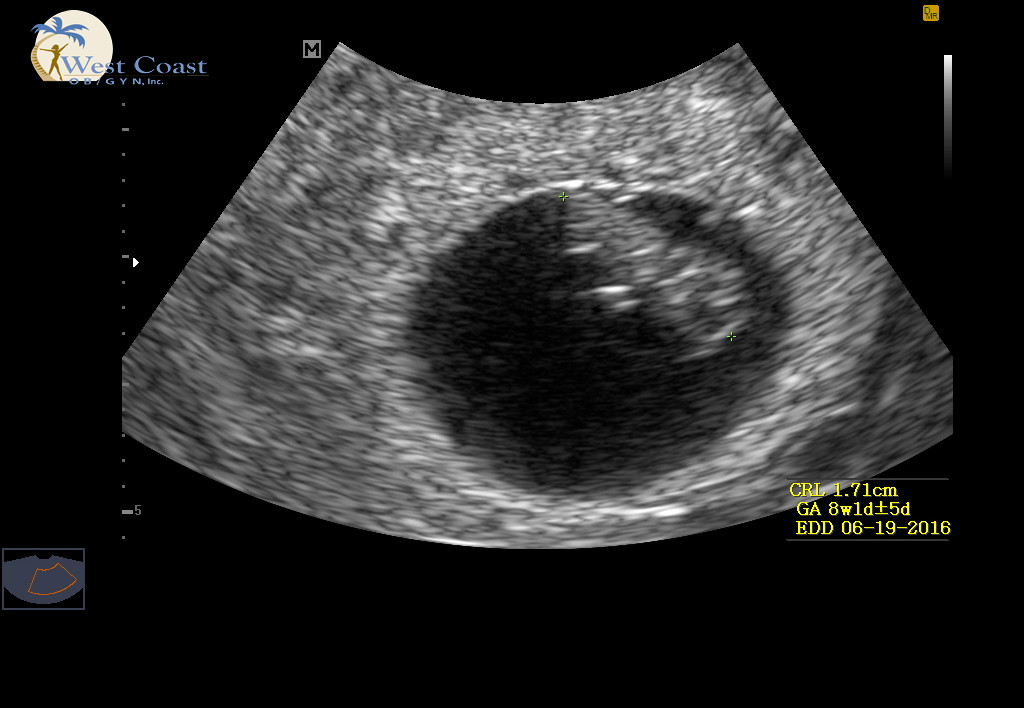

Had our first US today! Exactly 8w (LMP had me at 7w6d) and heart beat was a strong 163. All looks healthy & good. Next US is at 12w (NT scan). A bit relieved that all is well.